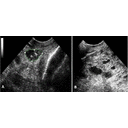

Image showing ultrasound of mammary gland.png